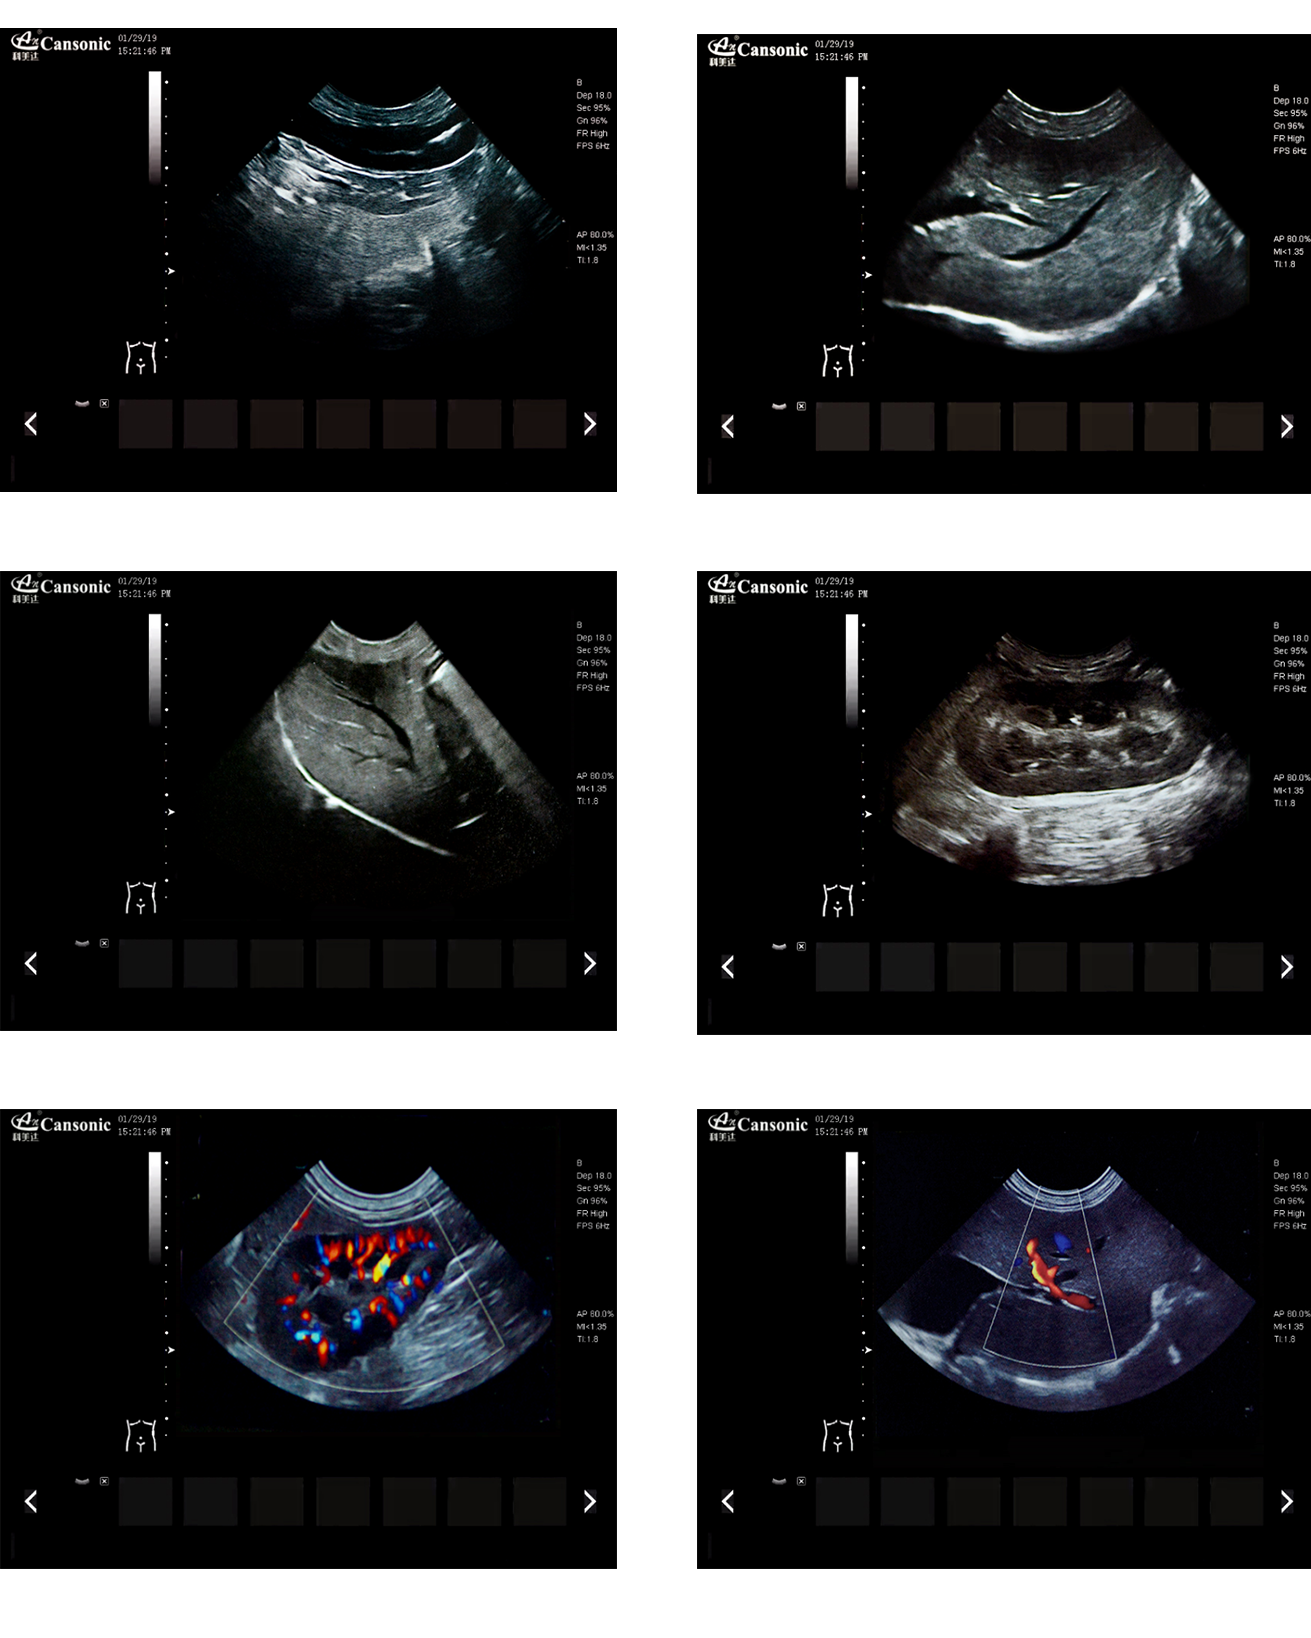

臨床圖示

1、薈萃前沿成像技術,實現高精與靈便的完美融合,提供完整的動物彩超診療方案

2、專業的獸用測量軟件,簡捷的工作流,適合犬、貓、馬、牛、羊等 各類大小動物

5、精細血流識別技術,增加了可疑病變更多的信息分析